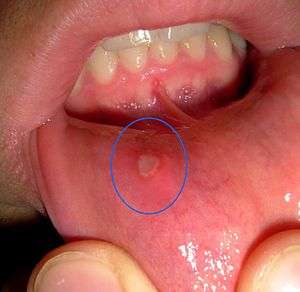

| A mouth ulcer (in this case associated with aphthous stomatitis) on the labial mucosa (lining of the lower lip). | |

A mouth ulcer is an ulcer that occurs on the mucous membrane of the oral cavity.[1] Mouth ulcers are very common, occurring in association with many diseases and by many different mechanisms, but usually there is no serious underlying cause.

The two most common causes of oral ulceration are local trauma (e.g. rubbing from a sharp edge on a broken filling) and aphthous stomatitis ("canker sores"), a condition characterized by recurrent formation of oral ulcers for largely unknown reasons. Mouth ulcers often cause pain and discomfort, and may alter the person's choice of food while healing occurs (e.g. avoiding acidic or spicy foods and beverages).

They may form individually or multiple ulcers may appear at the same time (a "crop" of ulcers). Once formed, the ulcer may be maintained by inflammation and/or secondary infection. Rarely, a mouth ulcer that does not heal may be a sign of oral cancer.

Aphthous stomatitis (also termed recurrent aphthous stomatits, RAS, and commonly called "canker sores") is a very common cause of oral ulceration. 10–25% of the general population suffer from this non-contagious condition. The appearance of aphthous stomatitis varies as there are 3 types, namely minor aphthous ulceration, major aphthous ulceration and herpetiform ulceration. Minor aphthous ulceration is the most common type, presenting with 1–6 small (2-4mm diameter), round/oval ulcers with a yellow-grey color and an erythematous (red) "halo". These ulcers heal with no permanent scarring in about 7–10 days. Ulcers recur at intervals of about 1–4 months. Major aphthous ulceration is less common than the minor type, but produces more severe lesions and symptoms. Major aphthous ulceration presents with larger (>1 cm diameter) ulcers that take much longer to heal (10–40 days) and may leave scarring. The minor and major subtypes of aphthous stomatitis usually produce lesions on the non-keratinized oral mucosa (i.e. the inside of the cheeks, lips, underneath the tongue and the floor of mouth), but less commonly major aphthous ulcers may occur in other parts of the mouth on keratinized mucosal surfaces. The least common type is herpetiform ulceration, so named because the condition resembles primary herpetic gingivostomatitis. Herpetiform ulcers begin as small blisters (vesicles) which break down into 2-3mm sized ulcers. Herpetiform ulcers appear in "crops" sometimes hundreds in number, which can coalesce to form larger areas of ulceration. This subtype may cause extreme pain, heals with scarring and may recur frequently.